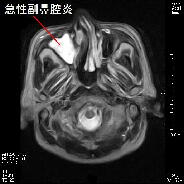

また緑内障など眼科的な問題で慢性的な頭痛を引き起こしている場合もありますし,耳鼻科的疾患である副鼻腔炎(蓄膿症)が原因となっている場合も結構見られます.最近はアレルギー性鼻炎の方が多く2次的に急性副鼻腔炎を引き起こしている方も多く見られます.左の写真は副鼻腔炎の症例ですが,正常例と比較すると膿の貯留により副鼻腔が白くなっています.これらの頭痛も検査をすればすぐに原因が判明します.このように頭痛の原因は思いもよらないところにある場合があり,慢性的な頭痛にお悩みの方は一度検査をお勧めします.